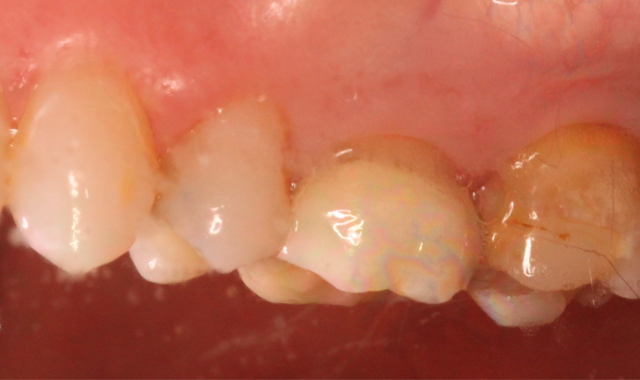

Fig. 1 Fig. 2

A 53-year-old male presented with a treatment plan to replace an existing f rst molar crown and prepare a crown on a second molar (Figs. 1-2).